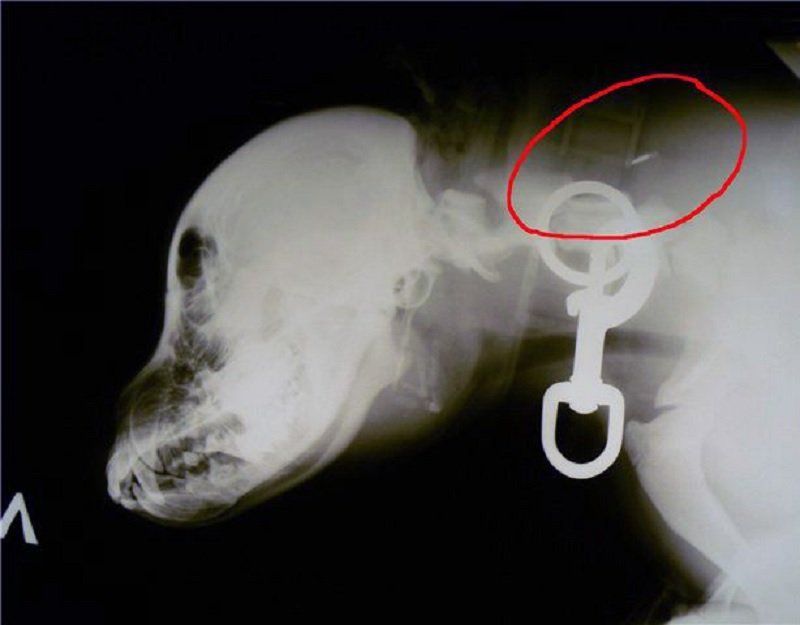

Чипирование — ввод под кожу животного импланта с идентификационным номером. Он в своем роде является паспортом любимца, по которому легко узнать информацию о его родословной, болезнях или прививках. Кроме того, наличие микрочипа обязательно при пересечении границы.

В правилах содержания животных Днепра прописано: все домашние собаки должны быть чипированы. Кошек это требование не коснулось. Хозяин сам решает, вводить ли под кожу своей мурки имплант. Зато данные зарегистрированных собак пообещали собрать в единую городскую базу, чтобы вести учет и контроль животных Днепра.

Чипировать своего питомца можно в ветклинике, которое имеет разрешение на это, либо в КП «Зооконтроль» - так говорится в правилах. Но за два месяца в коммунальном предприятии так и не запустили эту процедуру. Объясняют — еще не проплатили жетоны. Их на ошейнике должно носить каждое зарегистрированное в базе животное.

Уже с сегодняшнего дня собираются начать чипирование в «Зооконтроле». Стоить процедура будет 163 гривны (чип и жетон, подвязанный к городской базе животных). До 15 октября пенсионеры Днепра могут чипировать своих питомцев бесплатно.

Тем, кто уже чипировал свое животное до запуска правил, должен занести информацию о нем в городскую базу. Кроме того, в «Зооконтроле» необходимо получить жетон, который будет это подтверждать.